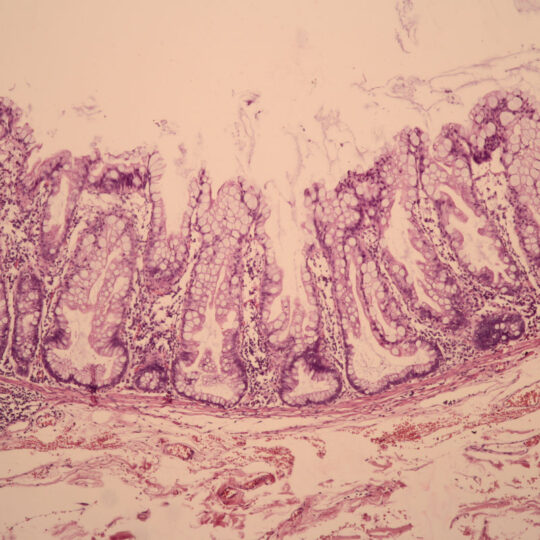

Na bioptickom úseku sa vykonáva štandardná diagnostika nádorových a nenádorových lézií rôznych orgánov, počnúc ochoreniami gastrointestinálneho traktu, ženského a mužského pohlavného systému, močového systému, ochorení hlavy a krku, nádorových ochorení CNS, kože, mäkkých tkanív a štítnej žľazy. Vyšetruje sa fixovaný materiál s použitím štandardných (HE), špeciálnych (Fe, PAS, Melaním VG, Ret…) a imunohistochemických farbiacich metód.

Celý proces sa začína fixáciou tkanív vložením do fixačného média už na oddelení, kde bola vzorka odobratá. Fixácia trvá približne 24 hod. Jej cieľom je konzervovanie tkanív, zabránenie ich rozkladu enzýmami (ktoré sa uvoľňujú po smrti bunky), zachovanie štruktúry tkaniva a jeho farbiacich vlastností. Ďalší deň po odbere a fixácii nasleduje vyšetrenie materiálu lekárom, popis orgánu a odber vzoriek, tzv. excízií. Nasleduje odvodnenie tkaniva a presýtenie parafínom. Túto činnosť vykonávajú špeciálne prístroje – tkanivové procesory, ktoré pracujú automaticky, v poobedňajších a v nočných hodinách. Na tretí deň sa vzorky zalievajú do parafínových blokov, nasleduje ich rezanie, farbenie a montovanie na podložné sklíčka.

Na tretí deň po odbere sú hotové histologické preparáty, ktoré vyšetrí lekár a určí diagnózu.